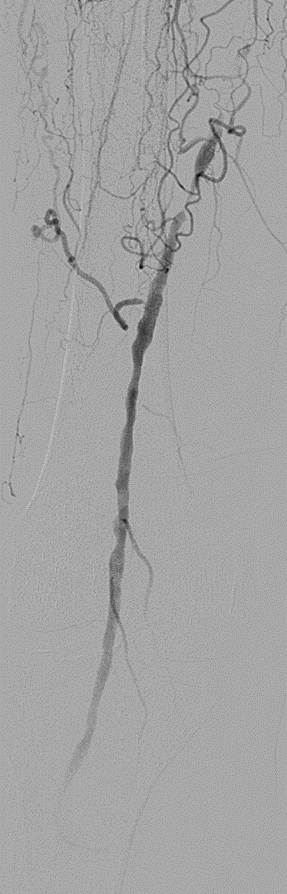

DEC 策略为下肢动脉长段 CTO 病变提供了一种创新的腔内解决方案。初步15例经验表明:

其一年期通畅率值得肯定,部分病例甚至实现了两年以上的完美通畅;

能有效克服夹层、recoil 和内膜增生等核心难题;

但仍需关注并发症(如远端栓塞、假性动脉瘤)及患者依从性。